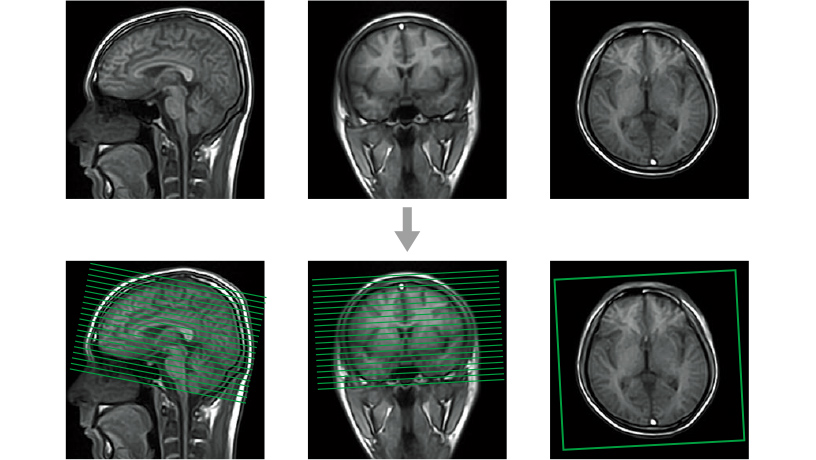

Інтелектуальна реконструкція

✓ SynergyDrive

✓ Глибоке навчання (DLR)

✓ Висока SNR

✓ Природна текстура зображення

- Автоматичне сканування